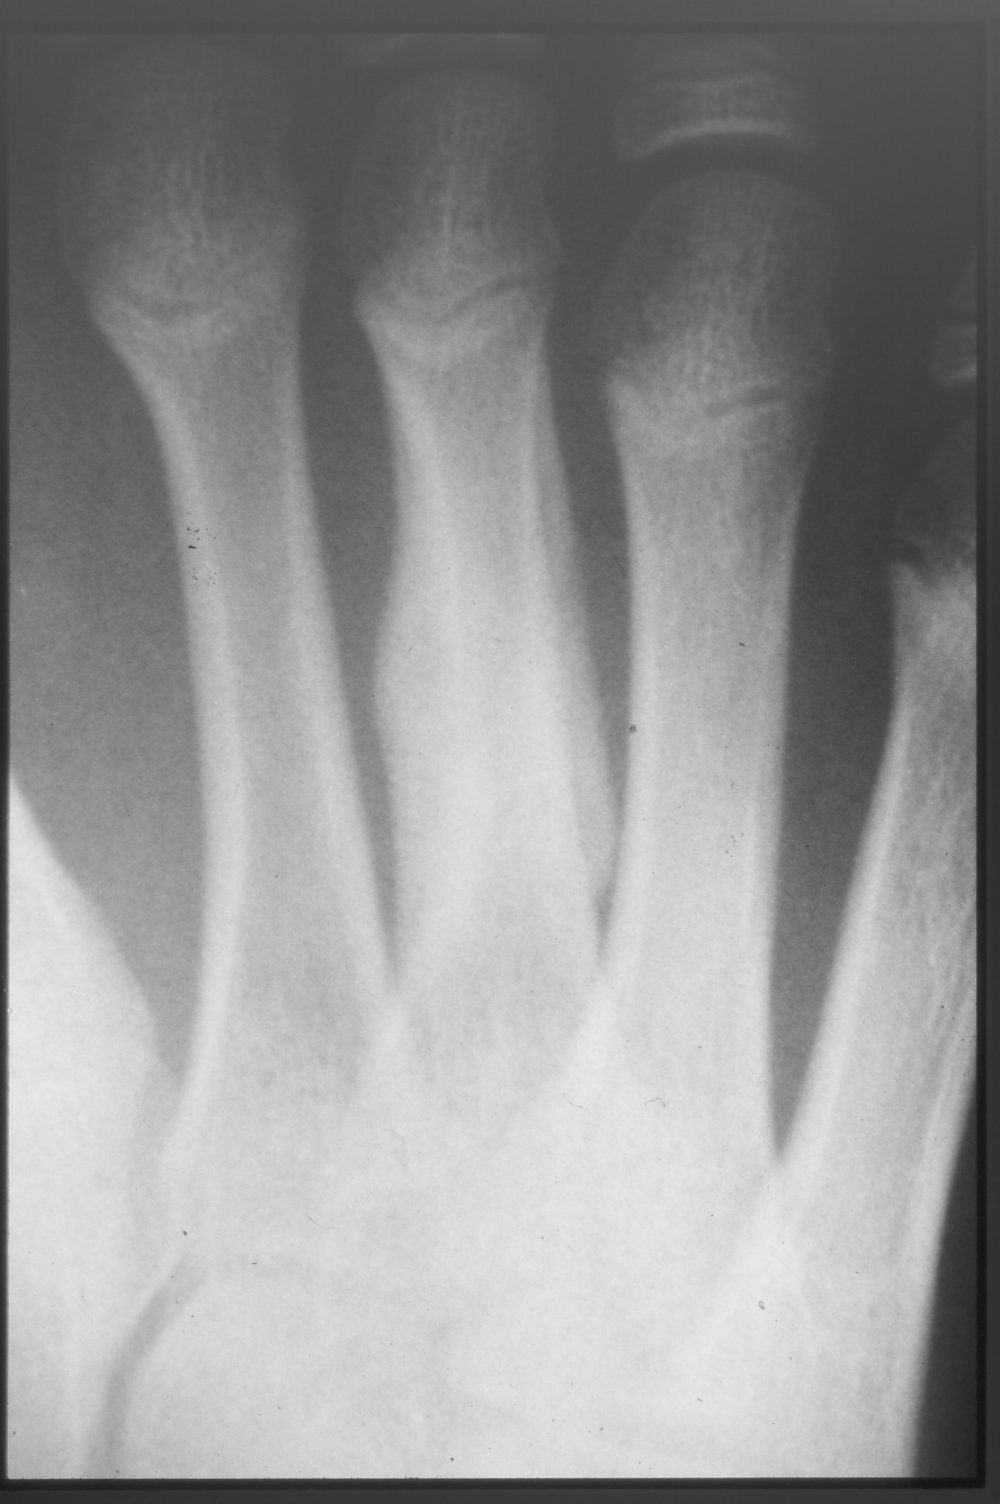

足指の疲労骨折

マラソンで、疲労骨折されました。完走されましたが、激痛だったそうです。